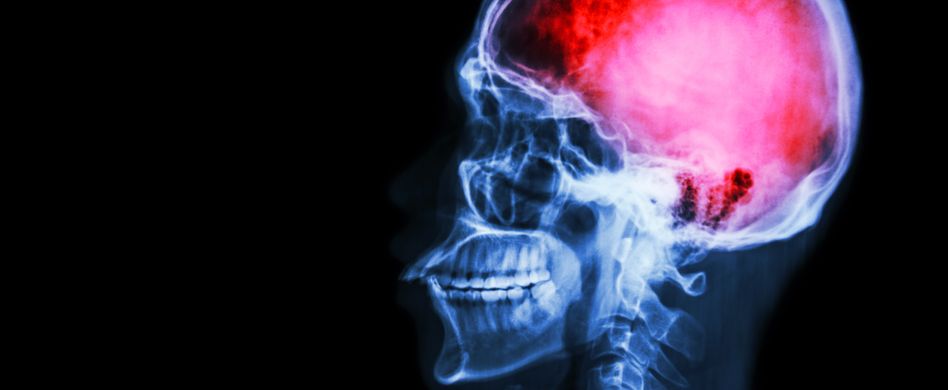

Das Gehirn ist groß und hat unzählige Funktionen. Ein Hirninfarkt kann überall darin stattfinden. Daher hängen bei einem Schlaganfall die Folgen davon ab, wo genau sich das Ereignis abspielt und wie wichtig dieses Gebiet ist. Sogar die Gehirnhälfte spielt dabei eine Rolle. Bei Rechtshändern sitzt das Sprachzentrum überwiegend in der linken Hirnhälfte, die zudem die rechte Körperseite motorisch versorgt. Daher gilt ein Schlaganfall der linken Gehirnhälfte aufgrund der Folgen Sprachstörungen und Lähmung der rechten Hand als besonders beeinträchtigend. Bei einem Schlaganfall der rechten Gehirnhälfte betreffen die Folgen häufig die räumliche Orientierung und das Gefühlsleben, das sich plötzlich völlig verändert.

Ganz anders sieht das aus, wenn grundlegende physiologische Funktionen betroffen sind. Ein im Hirnstamm oder Zwischenhirn erfolgender Schlaganfall endet oftmals tödlich. Dafür reicht ein kleiner Schaden beispielsweise in den Steuerungszentren von Atmung und Herz-Kreislauf aus. Bei einem hämorrhagischen Insult, das heißt einer Einblutung infolge eines gerissenen Hirngefäßes, kann der Hirndruck durch das Blut erheblich ansteigen und Probleme verursachen. Vor allem geplatzte Aneurysmen des Arterienrings an der Hirnbasis führen oft zum Tod, da sie kaum zu stillen sind. Insgesamt nimmt etwa ein Fünftel aller Schlaganfälle einen tödlichen Verlauf.

Bei einem Schlaganfall gehören zu den Folgen häufig Sehstörungen, Sprachstörungen und/oder einseitige Lähmungserscheinungen. Sie betreffen über zwei Drittel aller Patienten.Schädigt ein Schlaganfall das Kleinhirn, machen sich die Folgen durch Beeinträchtigungen des Gleichgewichtssinns und Störungen der hier koordinierten Bewegungsabläufe bemerkbar. Ein Kleinhirninfarkt führt nicht nur zu Bewegungsstörungen in Armen und Beinen, sondern auch in Augen- und Kehlkopfmuskulatur. Daher ist er häufig mit Sehstörungen und Sprachstörungen verbunden.Die Großhirnrinde macht einen erheblichen Teil des Gehirns aus und leidet daher überproportional oft an den Folgen eines Schlaganfalls. Hier gibt es weitere Regionen, die für Sprache, Sehen und Bewegungen zuständig sind. So werden hier die Sinneseindrücke der Augen zu einem Bild zusammengesetzt, die Sprache artikuliert und Bewegungen in Abstimmung mit den Augen abgeschätzt.